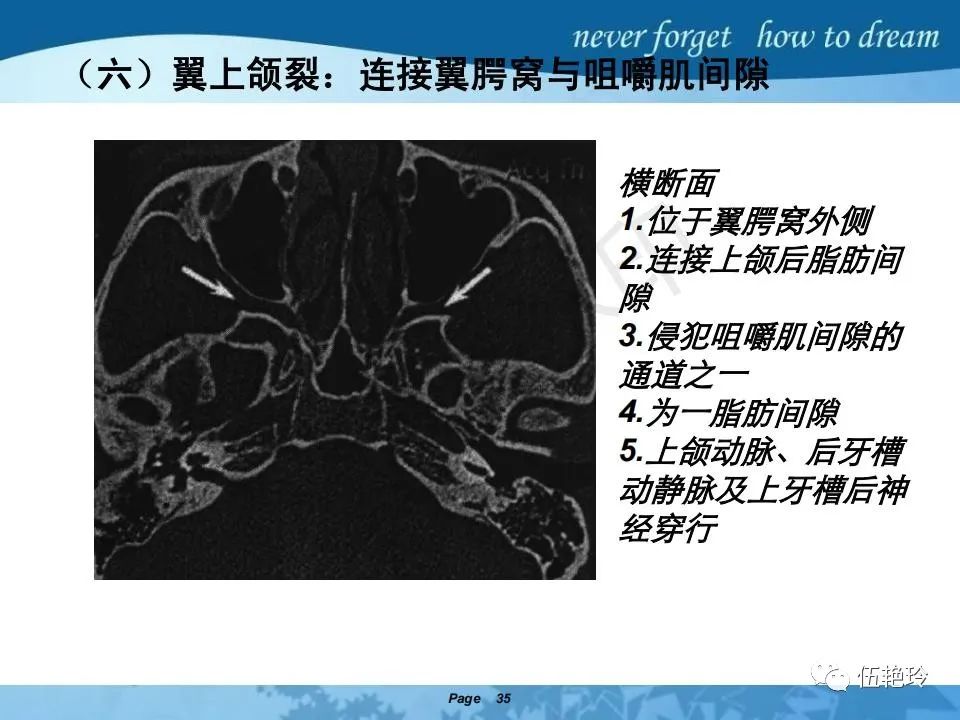

翼腭窝的解剖结构与鼻咽癌侵犯

颞下窝与咀嚼肌间隙

2.31 向上颅内:①鼻咽顶壁→破裂孔(岩尖、斜坡)→蝶窦、海绵窦;②鼻咽顶壁→蝶骨基底部→蝶窦、海绵窦;③鼻咽侧壁→茎突前间隙→蝶骨大翼(卵圆孔)→海绵窦;④鼻咽侧壁→茎突前间隙→翼腭窝→ 颞下窝;⑤鼻咽前壁→鼻腔→翼突、翼腭窝→眶下裂→眶尖→海绵窦;⑥鼻咽前壁→鼻腔→上颌窦、筛窦;